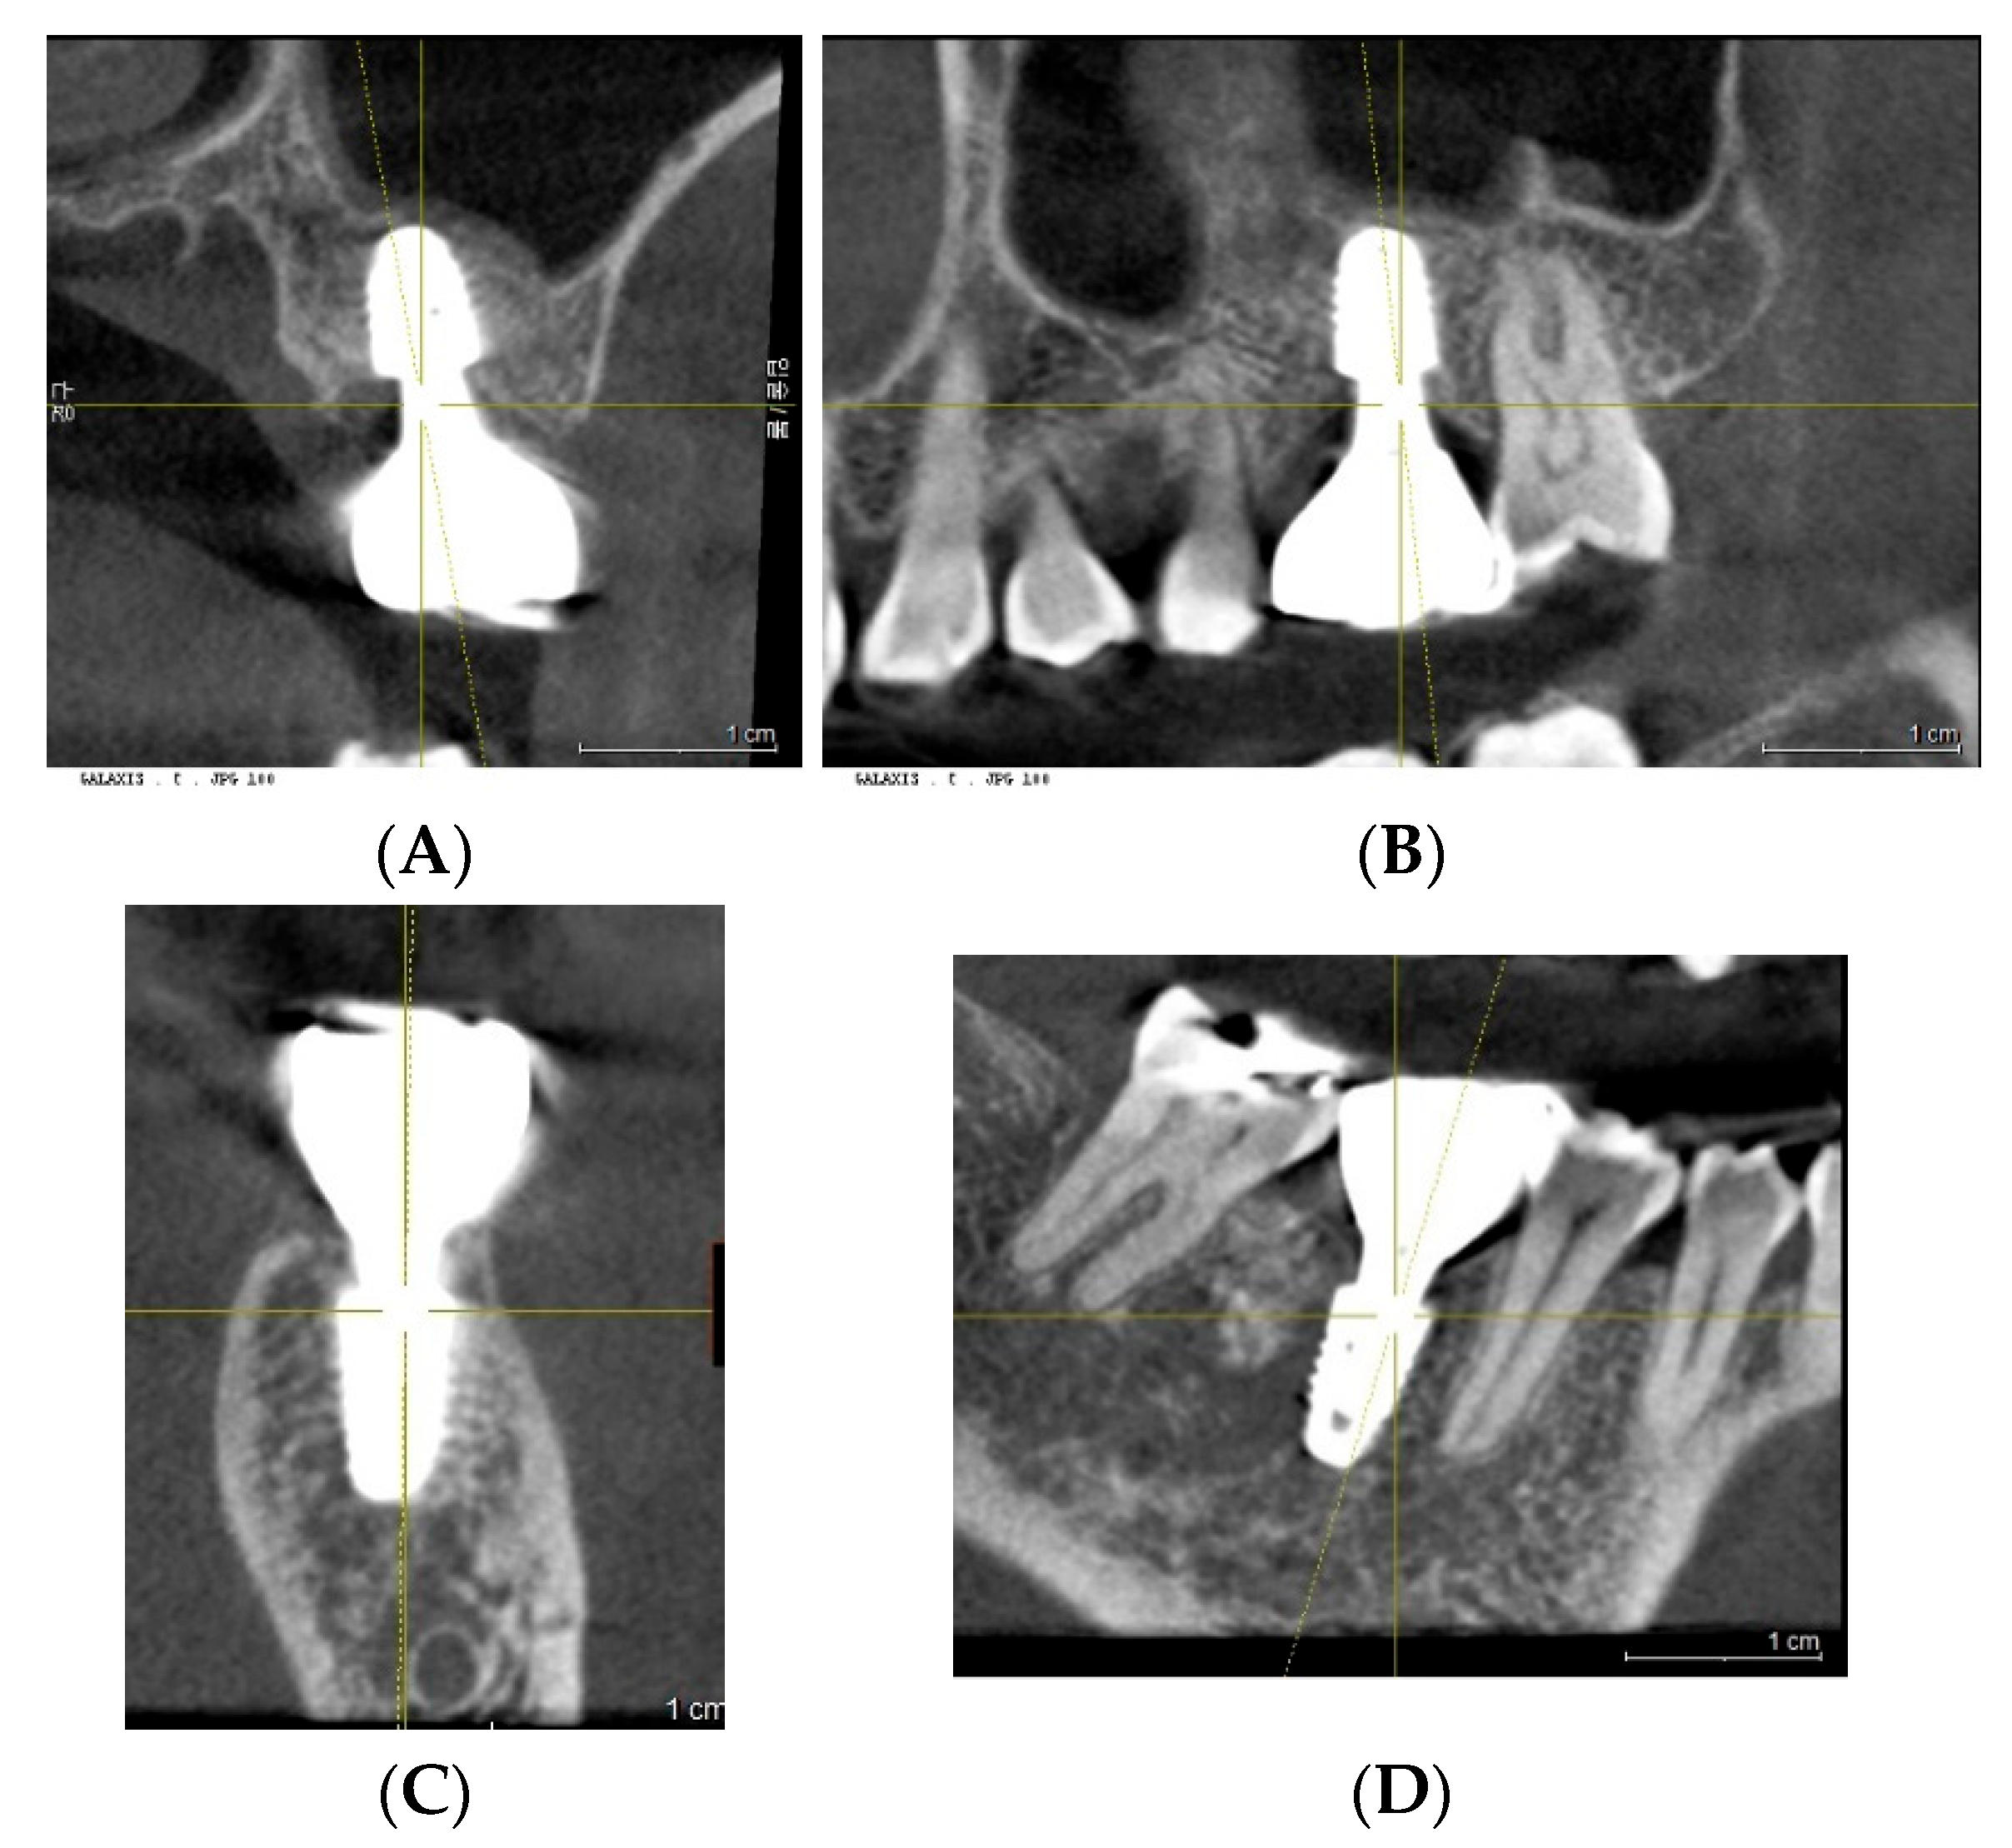

2. Case Presentation

3. Radiographic and Clinical Findings